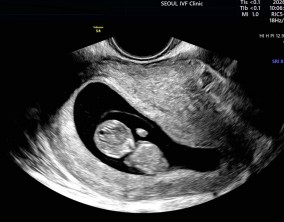

임신 수치 16, 9주차 기적의 기록

서울IVF에서는 단순히 배아 생성과 이식만 해주시는 것이 아니라, 제 생활 전반까지 신경 써주셨습니다. 휴식기에도 그저 기다리는 것이 아니라 항노화에 도움이 되는 링겔을 처방…